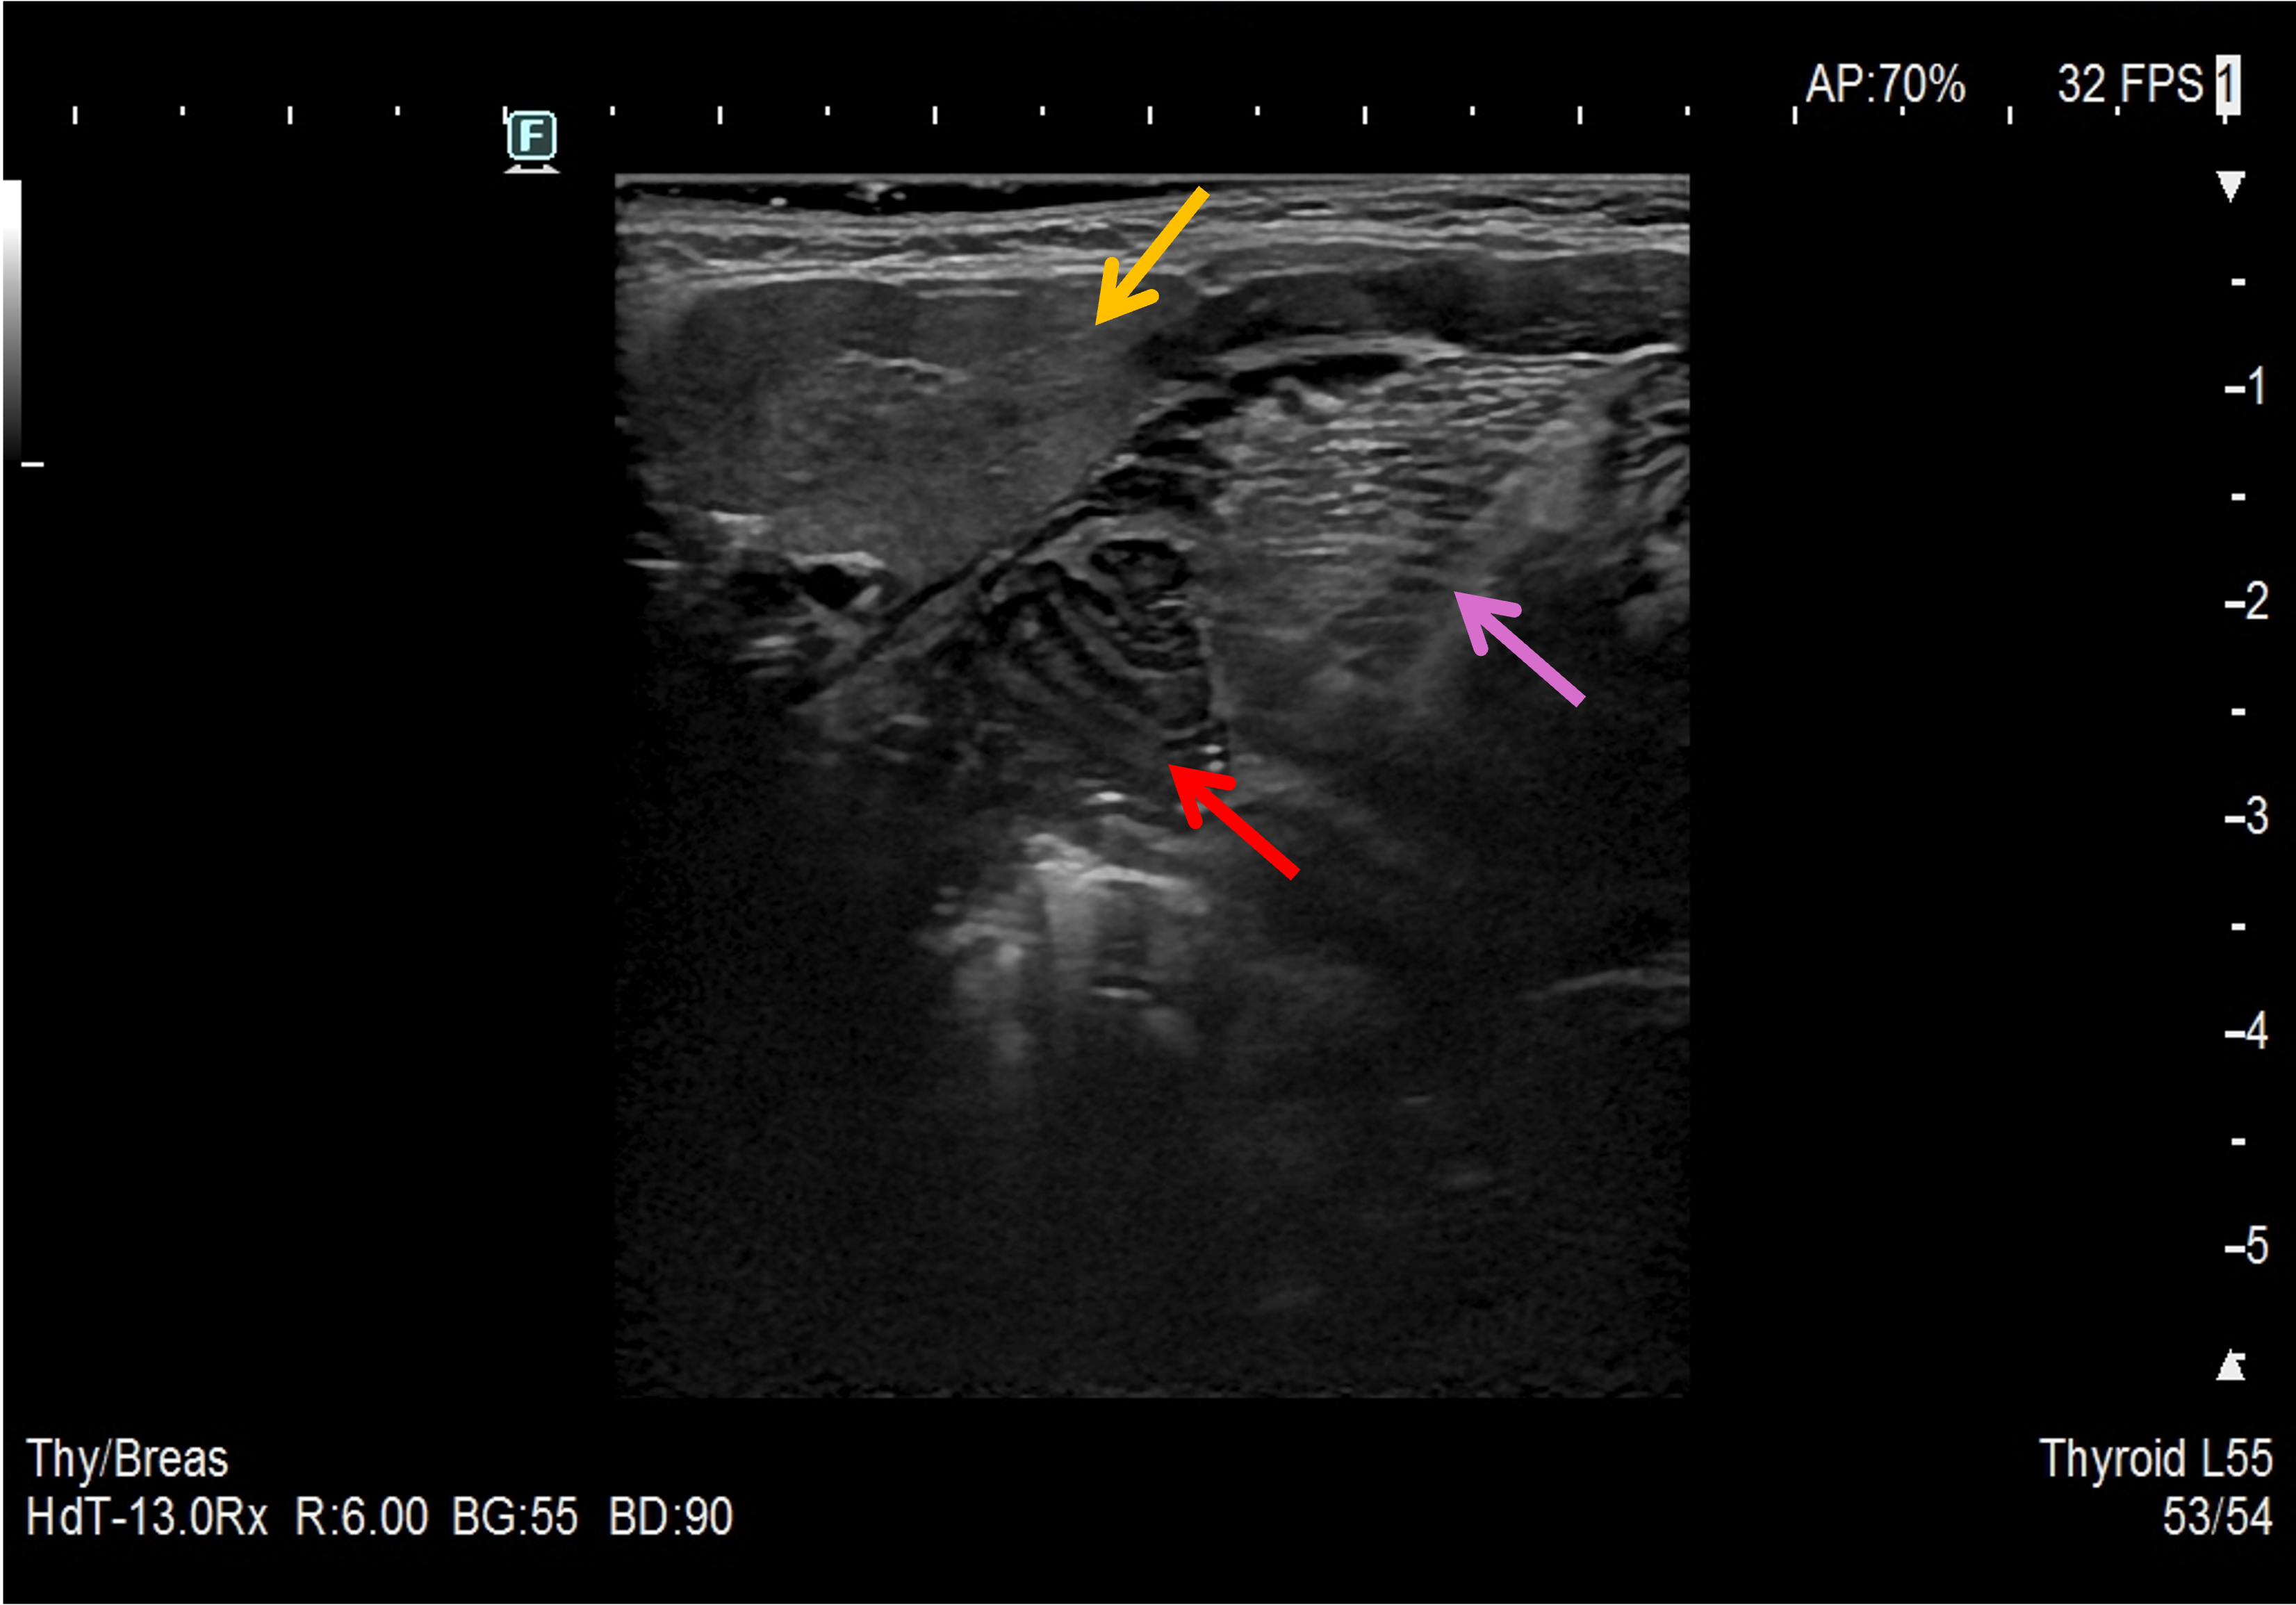

W USG ślinianki charakteryzują się echogenicznością wyższą od echogeniczności mięśni (zbliżoną do echogeniczności tkanki tłuszczowej oraz echogeniczności prawidłowego miąższu tarczycy) i jednorodną echostrukturą. W warunkach prawidłowych przewody wyprowadzające zazwyczaj są niewidoczne. Echogeniczność ślinianki podżuchwowej może być nieco niższa od echogeniczności ślinianki przyusznej. Unaczynienie prawidłowych ślinianek jest skąpe, a w przypadku ślinianek podjęzykowych często trudne do uwidocznienia.

Ślinianka przyuszna to największy, parzysty gruczoł ślinowy, zlokalizowany pomiędzy mięśniem żwaczem i mięśniem mostkowo-obojczykowo-sutkowym. Przez śliniankę przebiega tętnica szyjna zewnętrzna. Ślinianka przyuszna jest otoczona łącznotkankową torebką. Przewód wyprowadzający ślinianki (przewód Stenona lub przewód Stensena) biegnie od przedniego brzegu ślinianki, poniżej łuku jarzmowego, na powierzchni mięśnia żwacza, a następnie po przejściu przez ciało tłuszczowe policzka i mięsień policzkowy uchodzi do przedsionka jamy ustnej w okolicy trzonowców. W dystalnym odcinku przewodu może występować wariant anatomiczny w postaci ślinianki przyusznej dodatkowej. W miąższu prawidłowej ślinianki przyusznej można uwidocznić pojedyncze węzły chłonne. Należy pamiętać, że część głębokiego płata ślinianki jest przesłonięta przez żuchwę i może być niedostępna badaniu USG. Przewód wyprowadzający zwykle jest niewidoczny, choć czasem udaje się go uwidocznić w postaci bezechowej tubularnej struktury o średnicy <1 mm. Należy ocenić całą dostępną część miąższu ślinianki w płaszczyźnie poprzecznej (równoległej do trzonu żuchwy), przesuwając głowicę z góry ku dołowi oraz w płaszczyźnie czołowej, przesuwając głowicę od przodu do tyłu.

2. Prawidłowy miąższ ślinianki przyusznej.

3. Prawidłowy miąższ ślinianki przyusznej.

4. Prawidłowy miąższ ślinianki przyusznej. Na filmie widoczne bezechowe, tubularne struktury – przebiegająca przez śliniankę tętnica twarzowa.